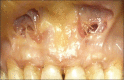

The containment of the elevator muscle of the upper lip and wing of nose was used for the treatment of patients with gummy smile. This technique had corrected esthetic alterations of smile, reducing the upper lip elevation, which results in a smaller gingival display. An upper lip lengthening as well as a reduction in the upper lip shortening when the patient smiled could be observed. The high smile line was corrected without compromising the labial harmony. This study presents an innovative and effective therapeutic option to obtain a natural and harmonious smile. The patient expressed a high degree of satisfaction.